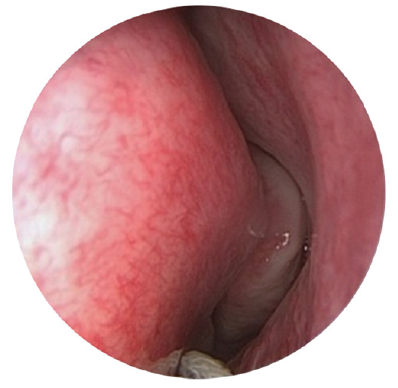

The study included patients with complaints of long-term lacrimation and suppuration (more than 6 months). The patients were diagnosed and treated at various institutions – at otorhinolaryngological and ophthalmological departments of the Pirogov State clinical hospital (Moscow) and hospitals of the MEDSI group of companies (Moscow) with the established diagnosis of “chronic dacryocystitis” during the period from 2015 to 2019. The clinical examination of patients included disease history, biomicroscopy of the anterior segment with evaluation of the eyelids, and anterior rhinoscopy. Endoscopic examination of the nasal cavity was performed using rigid endoscopes of 0° and 30° and 4 mm in diameter, after local application anesthesia with 10% lidocaine hydrochloride solution, with examination of all the endonasal structures of the nasal cavity: inferior nasal meatus, nasal floor, inferior nasal concha, middle nasal meatus, osteomeatal complex, area of the hamate bone, front end of the middle turbinate, and lacrimal tubercle of the nasal septum (Fig. 1–3).

Fig. 2. Endoscopy of the nasal cavity. Endoscope 4 mm 0°. The enlarged concha bullosa obstructs access to the operating field